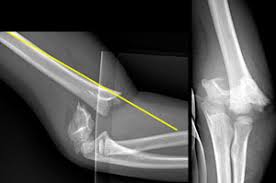

Dokter atau penyedia layanan kesehatan akan menanyakan bagimana cedera tersebut terjadi dan akan melakukan pemeriksaan lengkap untuk menilai nyeri, bengkak, dan sirkulasi atau aliran darah pada sisi yang mengalami cedera. Foto rontgen akan dilakukan untuk melihat apakah tulang mengalami pergeseran.